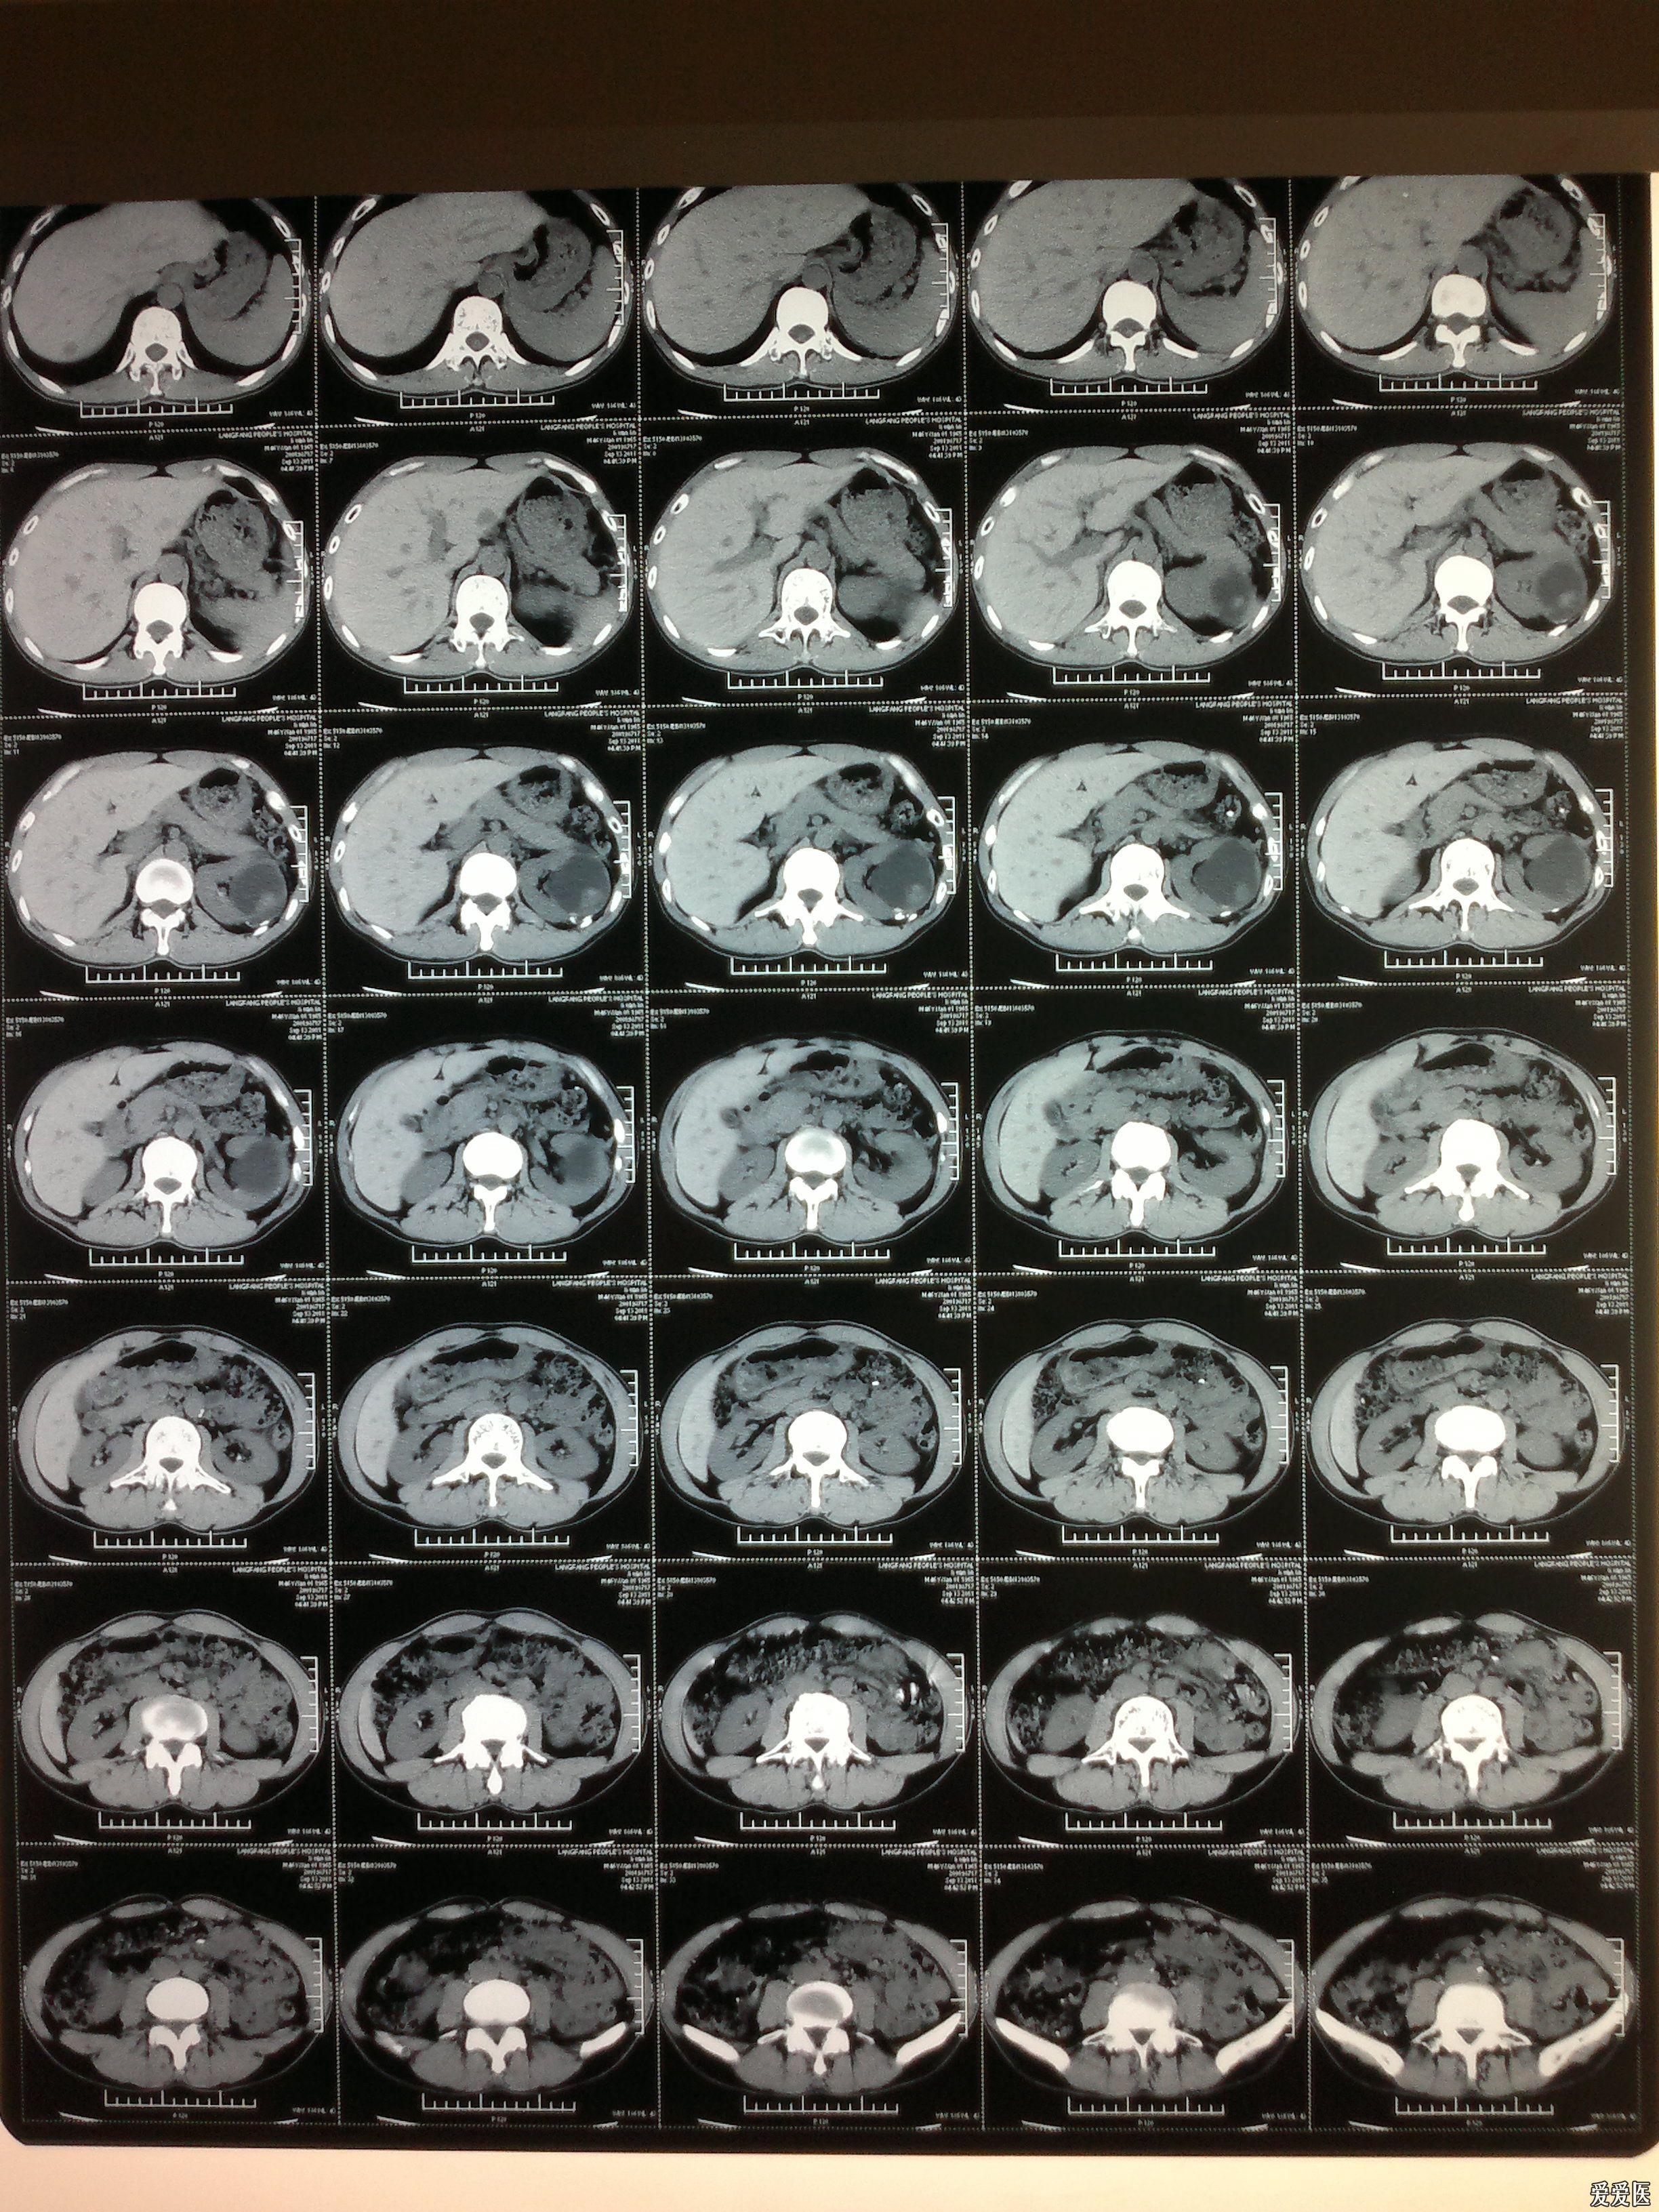

肾挫伤保守一个月结果

图片尺寸2448x3264